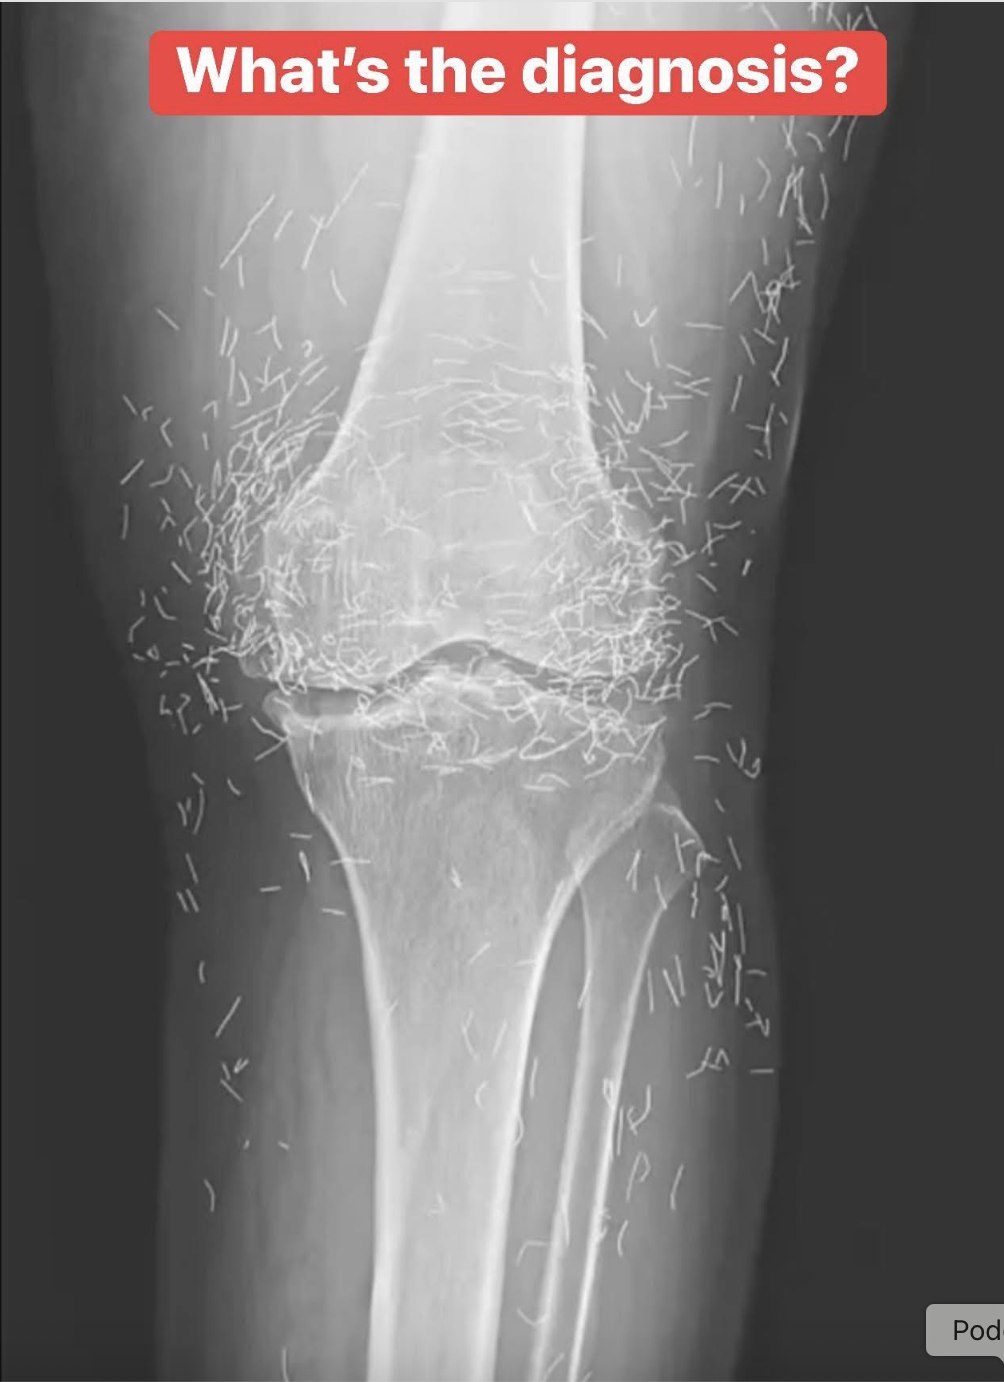

When a 65-year-old woman from South Korea sought treatment for knee pain, the doctors did not expect to find something extraordinary. However, that is exactly what they discovered.

Consequently, she sought acupuncture, as reported in a case published in the New England Journal of Medicine.

Acupuncture, an alternative treatment with a history spanning centuries, entails the insertion of needles into specific points on the body to alleviate pain or address various health issues. In this particular instance, the needles—likely crafted from gold—were deliberately left in her knees to provide ongoing stimulation.

The evidence supporting the efficacy of acupuncture in treating medical conditions is scarce. Nevertheless, it continues to be a favored choice for alleviating joint pain, particularly in certain Asian nations where the practice of inserting small pieces of sterile gold thread around a joint is a prevalent treatment for arthritis.

For this woman, her knees adorned with gold serve as a poignant reminder that at times, alternative medicine can leave more than just a mark — it can result in a literal treasure trove.